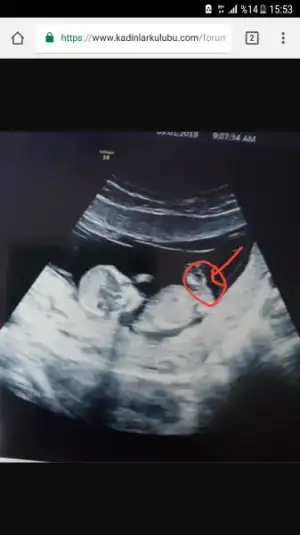

ben baska arkadasa ultrason goruntusunden genital nub tahmini yapmistim tutmus. Ama bir turlu kendiminkini bilemiyorum ya nasil bir kisiligim var anlamadim gitti :KK45: